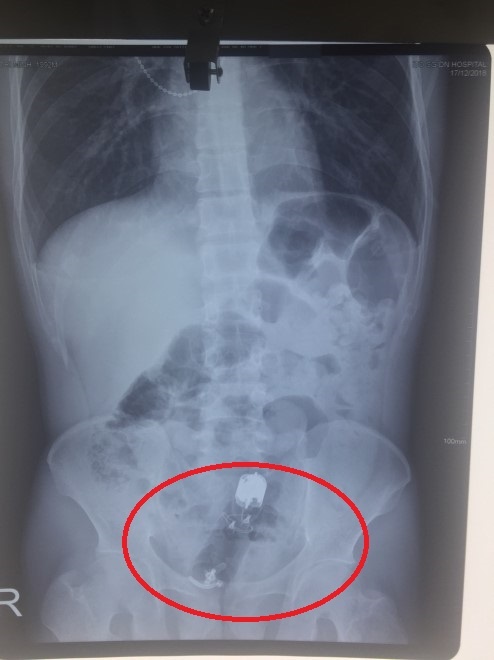

| Dị vật nằm sâu trong trực tràng bệnh nhân. Ảnh: BVCC. |

Đau tức hậu môn, 3 ngày không thể đi đại tiện, Nguyễn Văn Quang (26 tuổi, Đồng Nai) đến bệnh viện chụp X-quang và nội soi. Các bác sĩ phát hiện dị vật là một dương vật giả có kích thước tới 18 cm bị nhét sâu trong hậu môn khoảng 10 cm.